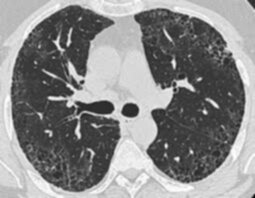

Demirci, pulmoner fibrozisin tanısal sürecinde tüm aşamaların eksiksiz yapılabilmesinin önemine dikkat çekerek, şu çağrıyı yaptı: “Uyum içinde çalışan multidisipliner ekiplerin olduğu merkez sayılarının artması önemli. Eğer bu merkezler artarsa, akciğer sertleşmesi hastalarının doğru tanı süreci kolaylaşır. Akciğer sertleşmesi tanı ve takibinde ayrıntılı solunum fonksiyon testleri, tekniğine uygun çekilen akciğer bilgisayarlı tomografisi ve romatolojik kan tahlilleri gerekir. Bunları doğru yapılabilen merkezlerin yaygınlaştırılması şart. Akciğer sertleşmesinde tedavi süreci sigaranın bırakılması, sertleşmeyi yavaşlatmaya yönelik- antifibrotik ilaçlar olan pirfenidon ve nintedanib kullanımı, oksijen tedavisi, pulmoner rehabilitasyon, aşılama, akciğer nakli ve yeni ilaç çalışmalarına hastaların yönlendirilmesi gibi çok yönlü bir süreci kapsar. Pulmoner rehabilitasyon ve akciğer nakli yapan merkezlerin yaygınlaştırılmasıyla akciğer sertleşmesi bulunan hastaların bu imkanlara rahatlıkla ulaşabilmesi sağlanabilir.”

Akciğerlerin hastalık nedeniyle sertleşmesi nedeniyle esnekliğini kaybettiğini ve oksijenin vücuda geçişinin zorlandığını aktaran Demirci, pulmoner fibrozisin ayırt edici belirtileri ve tedavi süreciyle ilgili de şu bilgileri verdi: “Bu durum hastalarda başlangıçta efor sırasında, daha sonra da istirahatte belirginleşen nefes darlığı ve kuru öksürüğe sebep olur. Bu hastalar muayene edildiğinde akciğer sertleşmesinin tipik bulguları olan çıtırtı sesleri duyulabilir.”